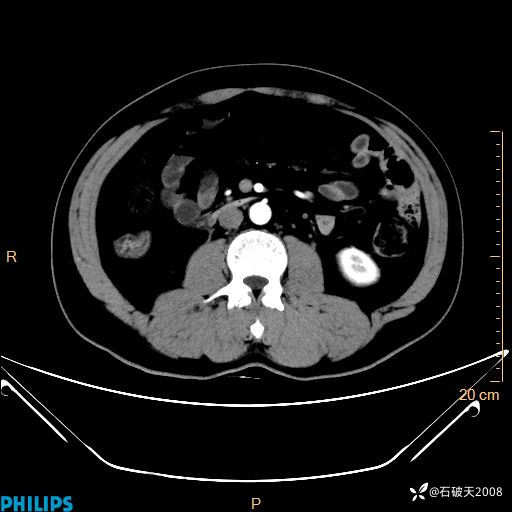

平扫轴位